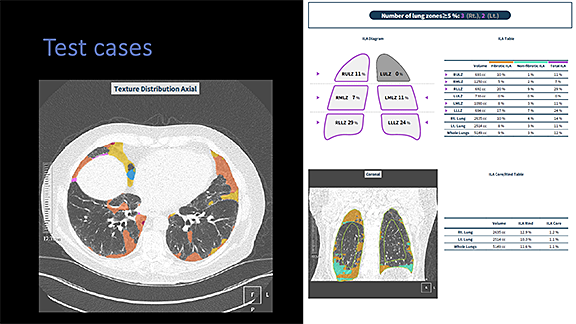

Brian Smiley, MD – Automated Pattern Analysis in the Diagnosis of Combined Pulmonary Fibrosis and Emphysema (CPFE). The goal of this project is to ascertain if artificial intelligence can assist in quantifying emphysema and fibrosis in the setting of CPFE. Coreline was initially brought to UMass for lung nodule detection for the lung screening program. Their aview: Lung Texture analysis will be used to attempt to quantify lung disease and distinguish between many particularly difficult findings, such as honeycombing, traction bronchiolectasis, and mosaic attenuation.